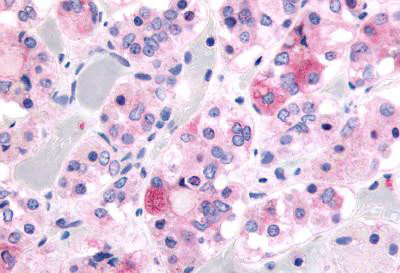

Immunohistochemistry (Formalin/PFA-fixed paraffin-embedded sections) - Anti-Ghrelin Receptor/GHS-R antibody (AB150514)

Immunohistochemistry of formalin-fixed, paraffin-embedded Human pituitary anterior tissue labelling Ghrelin Receptor/GHS-R with ab150514 at 5 μg/ml.